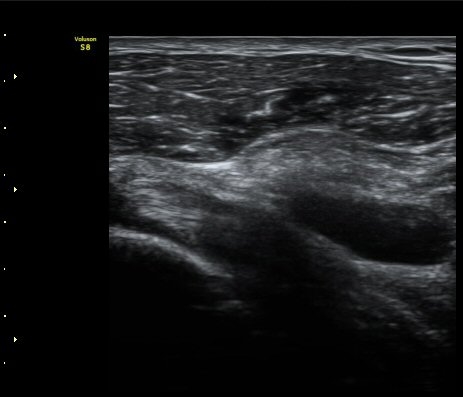

À̵ιڱ٠Á¾´Ü¸é°Ë»ç»ó ƯÀÌ ¼Ò°ßÀ» º¸ÀÌÁö ¾ÊÀ¸³ª(±×¸² 1)  ŽÃËÀÚ¸¦ ¾Æ·¡·Î À̵¿ÇÏ´Ï